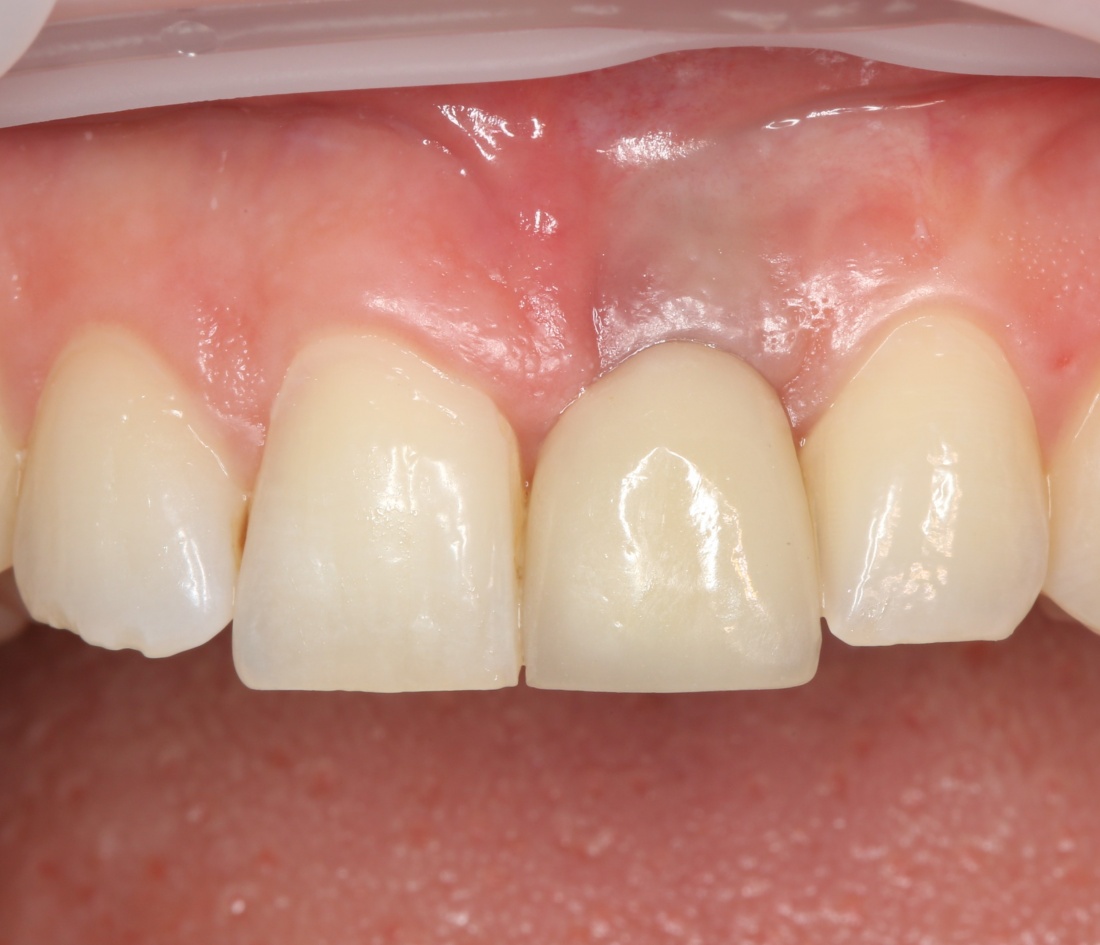

которая через три месяца, к моменту интеграции импланта, выглядит совсем иначе:

Ну и… к моменту установки постоянной коронки, у нас сохранился естественный контур прилегающей десны.

Что, собственно, нам и требовалось сделать.